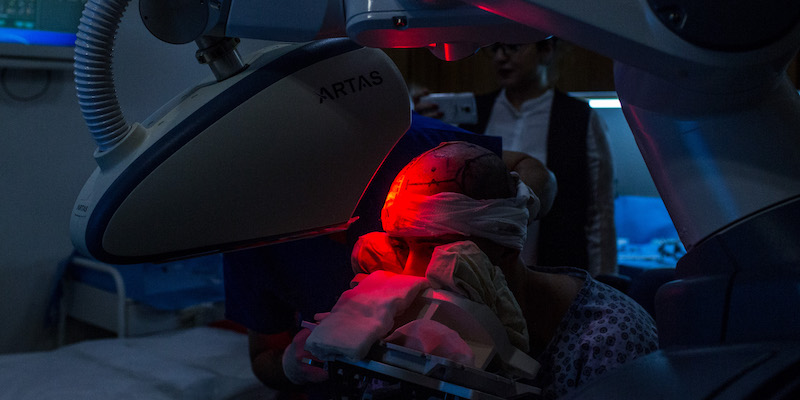

Fatte tutte le valutazioni del caso si passa all’operazione vera e propria, la cui durata varia a seconda delle tecniche utilizzate e della quantità di capelli da trapiantare. I capelli del paziente vengono rasati fino a 2 millimetri di lunghezza, in modo da poter osservare chiaramente l’orientamento dei follicoli e la loro angolazione. Lo scalpo viene anestetizzato e le strade seguite sono poi due a seconda del tipo di intervento: in un certo senso ricordano entrambe un travaso di piante, ma con un po’ di sangue.

Nel caso del metodo FUT (trapianto di unità follicolari) il chirurgo asporta una striscia di cuoio capelluto nella parte posteriore della testa lunga tra i 15 e i 30 centimetri e alta circa un centimetro, raggiungendo una profondità di 2-4 millimetri. La ferita viene poi chiusa con i punti, mentre a parte inizia la selezione delle unità follicolari dalla striscia di pelle appena asportata. La cernita viene effettuata al microscopio e deve essere fatta molto delicatamente, eliminando la parte di pelle che non serve senza danneggiare le cellule dei follicoli. Utilizzando poi minuscole lame, il chirurgo crea delle piccole incisioni nelle zone della testa dove la calvizie è evidente in cui saranno innestati i follicoli, mantenendo la stessa inclinazione e orientamento di quelli naturalmente già presenti nella zona.

Il metodo alternativo più impiegato è il FUE (estrazione di unità follicolari) che non prevede di asportare un’intera striscia di pelle, ma di rimuovere una per una le unità follicolari da trapiantare. Uno strumento crea una incisione intorno all’unità follicolare, arrivando a una profondità di circa 4 millimetri, in seguito questa viene estratta e poco dopo collocata nella nuova posizione sulla testa (il video è piuttosto esplicito, avvisati).

Il FUE richiede solitamente più tempo per essere svolto rispetto al FUT, dove con una sola asportazione si ottengono molte unità follicolari per il trapianto. In compenso l’operazione è meno invasiva e non lascia una cicatrice come nella FUT, che viene comunque nascosta dai capelli, ma al tempo stesso è mediamente più costosa proprio per il maggior tempo richiesto per l’intervento. Entrambe le tecniche presentano vantaggi e svantaggi ed è ancora dibattuto se effettivamente una pratica sia meglio dell’altra.

A seconda delle caratteristiche dei capelli del paziente, della loro disponibilità nell’area donatrice e di altri parametri, la quantità di unità follicolari trapiantate varia molto. In media in un primo intervento il trapianto riguarda almeno 2mila unità, ma ci sono casi in cui possono essere necessarie più di 3mila unità. Da tempo si parla di future tecniche basate sull’impiego di cellule staminali (cellule non differenziate che possono poi assumere determinate funzioni), o di ingegneria genetica per clonare i follicoli, ma i progressi vanno a rilento, mentre si sono affinate tecniche e strumentazioni soprattutto legate al metodo FUE.

Al termine dell’operazione, il cuoio capelluto viene disinfettato e successivamente bendato per evitare che le ferite si infettino. La maggior parte dei pazienti indica i primi giorni post operazione come i più fastidiosi, a causa del bruciore e delle pratiche da seguire per evitare danni al trapianto: dormire solo in certe posizioni, medicare le ferite con grande delicatezza e cose di questo genere. Di solito viene prescritto un ciclo di antibiotici per ridurre ulteriormente il rischio di infezioni, che potrebbero danneggiare le unità follicolari da poco trapiantate.